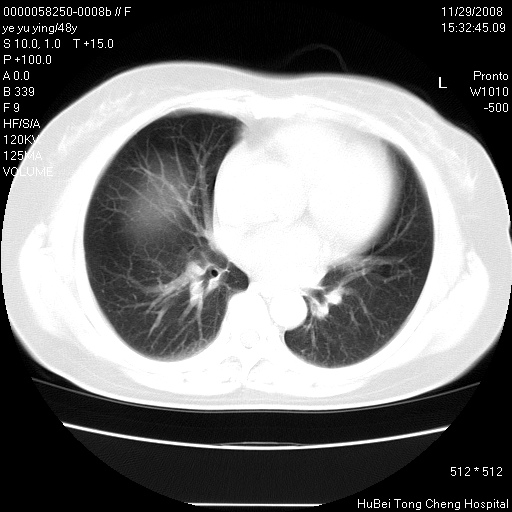

以下是引用huenhao在2008-11-29 22:11:00的发言:[br]脂肪肝,胆囊结石。左肺病灶建议定期复查。

以下是引用liuyue在2008-11-30 5:44:00的发言:[br]1.左肺病变,首先考虑感染性病变,转移待排;建议治疗后复查。[br]2.肝脏密度普遍减低,考虑与化疗有关。[br]3.胆囊结石.